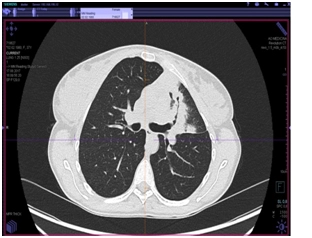

КТ органов грудной клетки (от 17.08.2017 г.)

Заключение: массивные инфильтративные изменения в верхней доле левого легкого полностью неясного генеза, возможно имеет место как воспалительный специфический характер поражения с распадом, так и осложнение пневмонии с формированием абсцесса, злокачественный процесс с распадом мало вероятен.